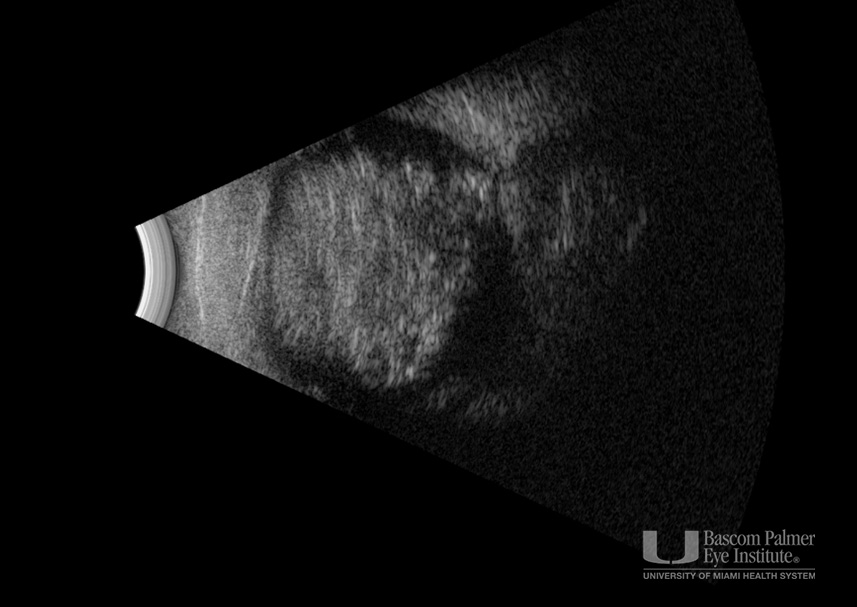

Bilateral retinoblastoma.

Bilateral Retinoblastoma